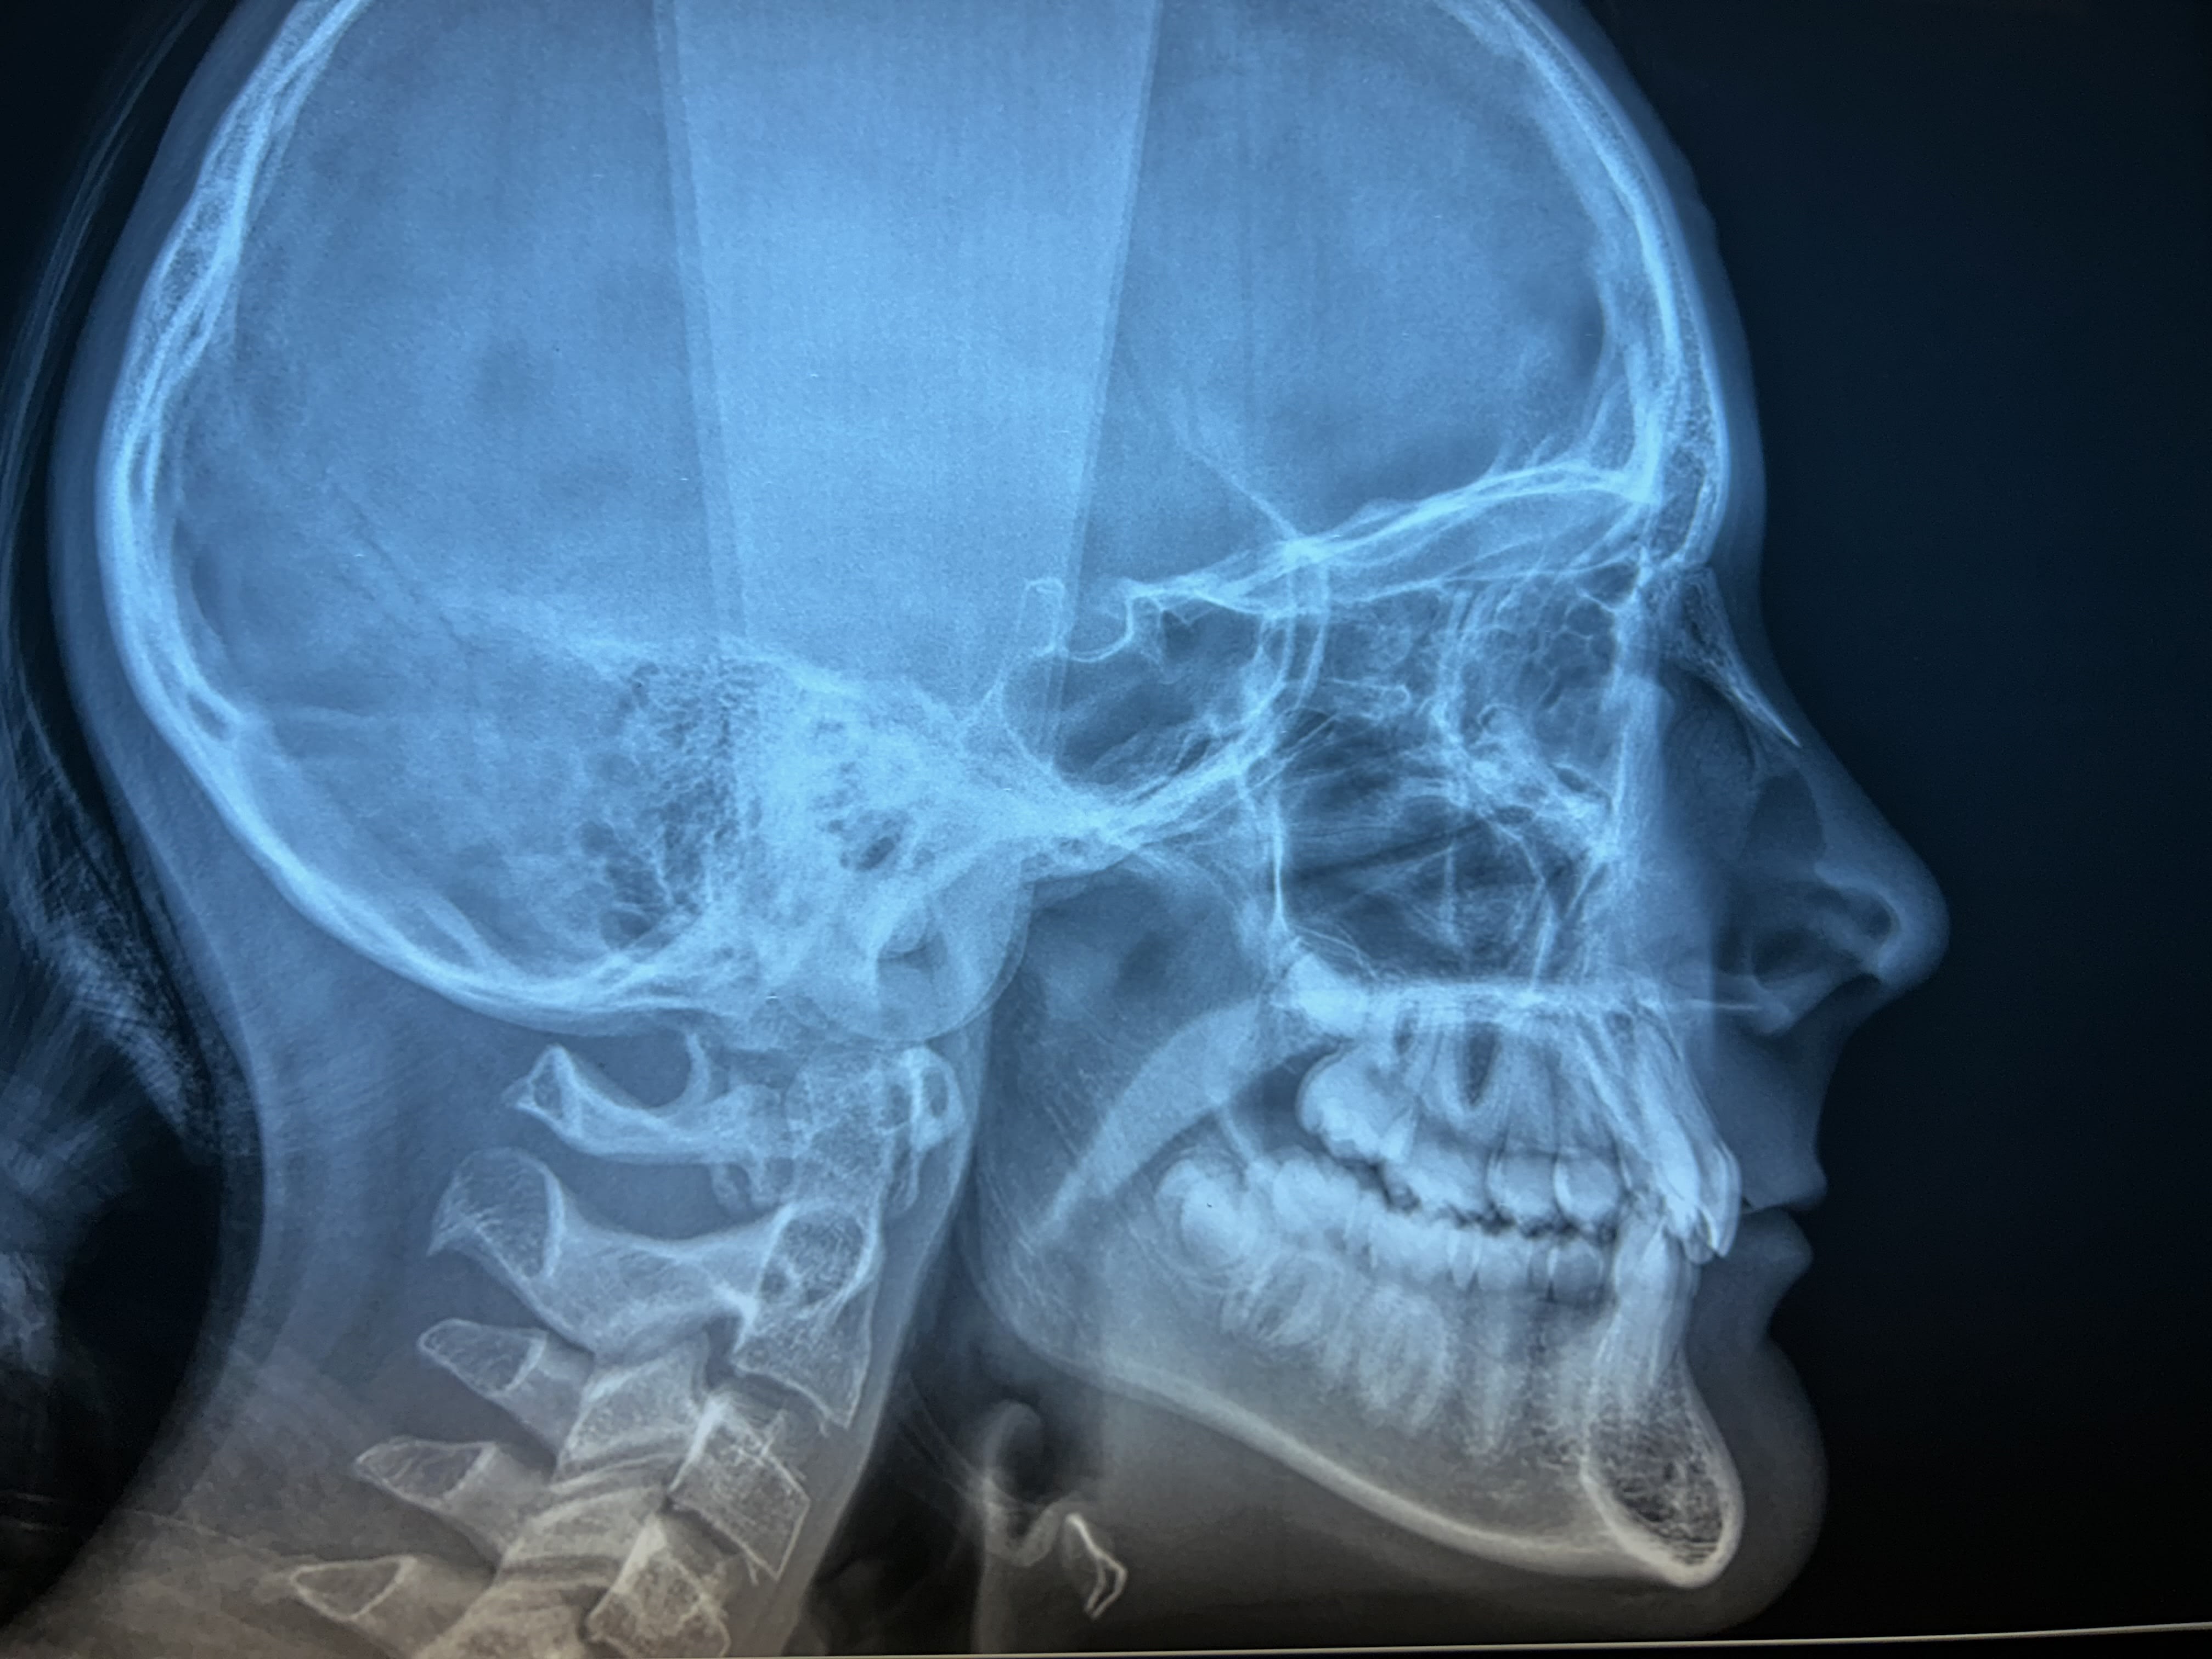

Jeune fille de 11 ans et demi, hypodivergente tendance classe III squelettique (mais classe II dentaire) et biretroalveolie. Agénésie de 12 avec évolution de 13 à sa place et 22 rhyziforme.

Le profil très rétrusif, la typologie verticale, et la supraclusion sont des éléments en faveur de l’ouverture d’espace afin de contrôler au mieux la position de l’incisive maxillaire.